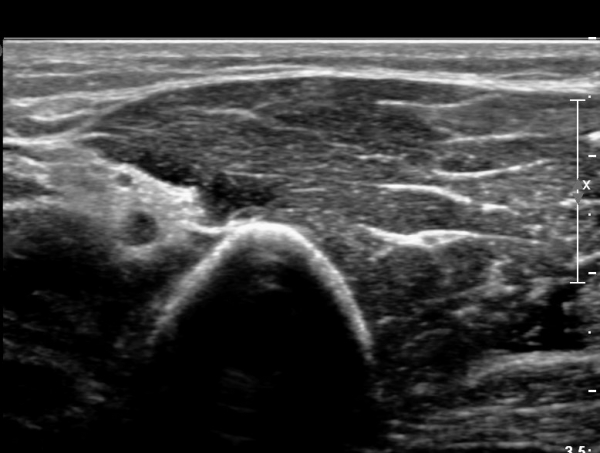

Á¶±Ý ´õ ¸»´ÜÀ¸·Î À̵¿ÇÏ´Ï ´Ù½Ã Àú¿¡ÄÚ ºÎÁ¾ »óÅ·Π°üÂûµÈ´Ù(»çÁø 4).

ÀÌ·± ÀÏ·ÃÀÇ °úÁ¤Àº ÷ºÎ µ¿¿µ»ó¿¡¼­ ¶Ñ·ÈÈ÷ °üÂûµÈ´Ù.